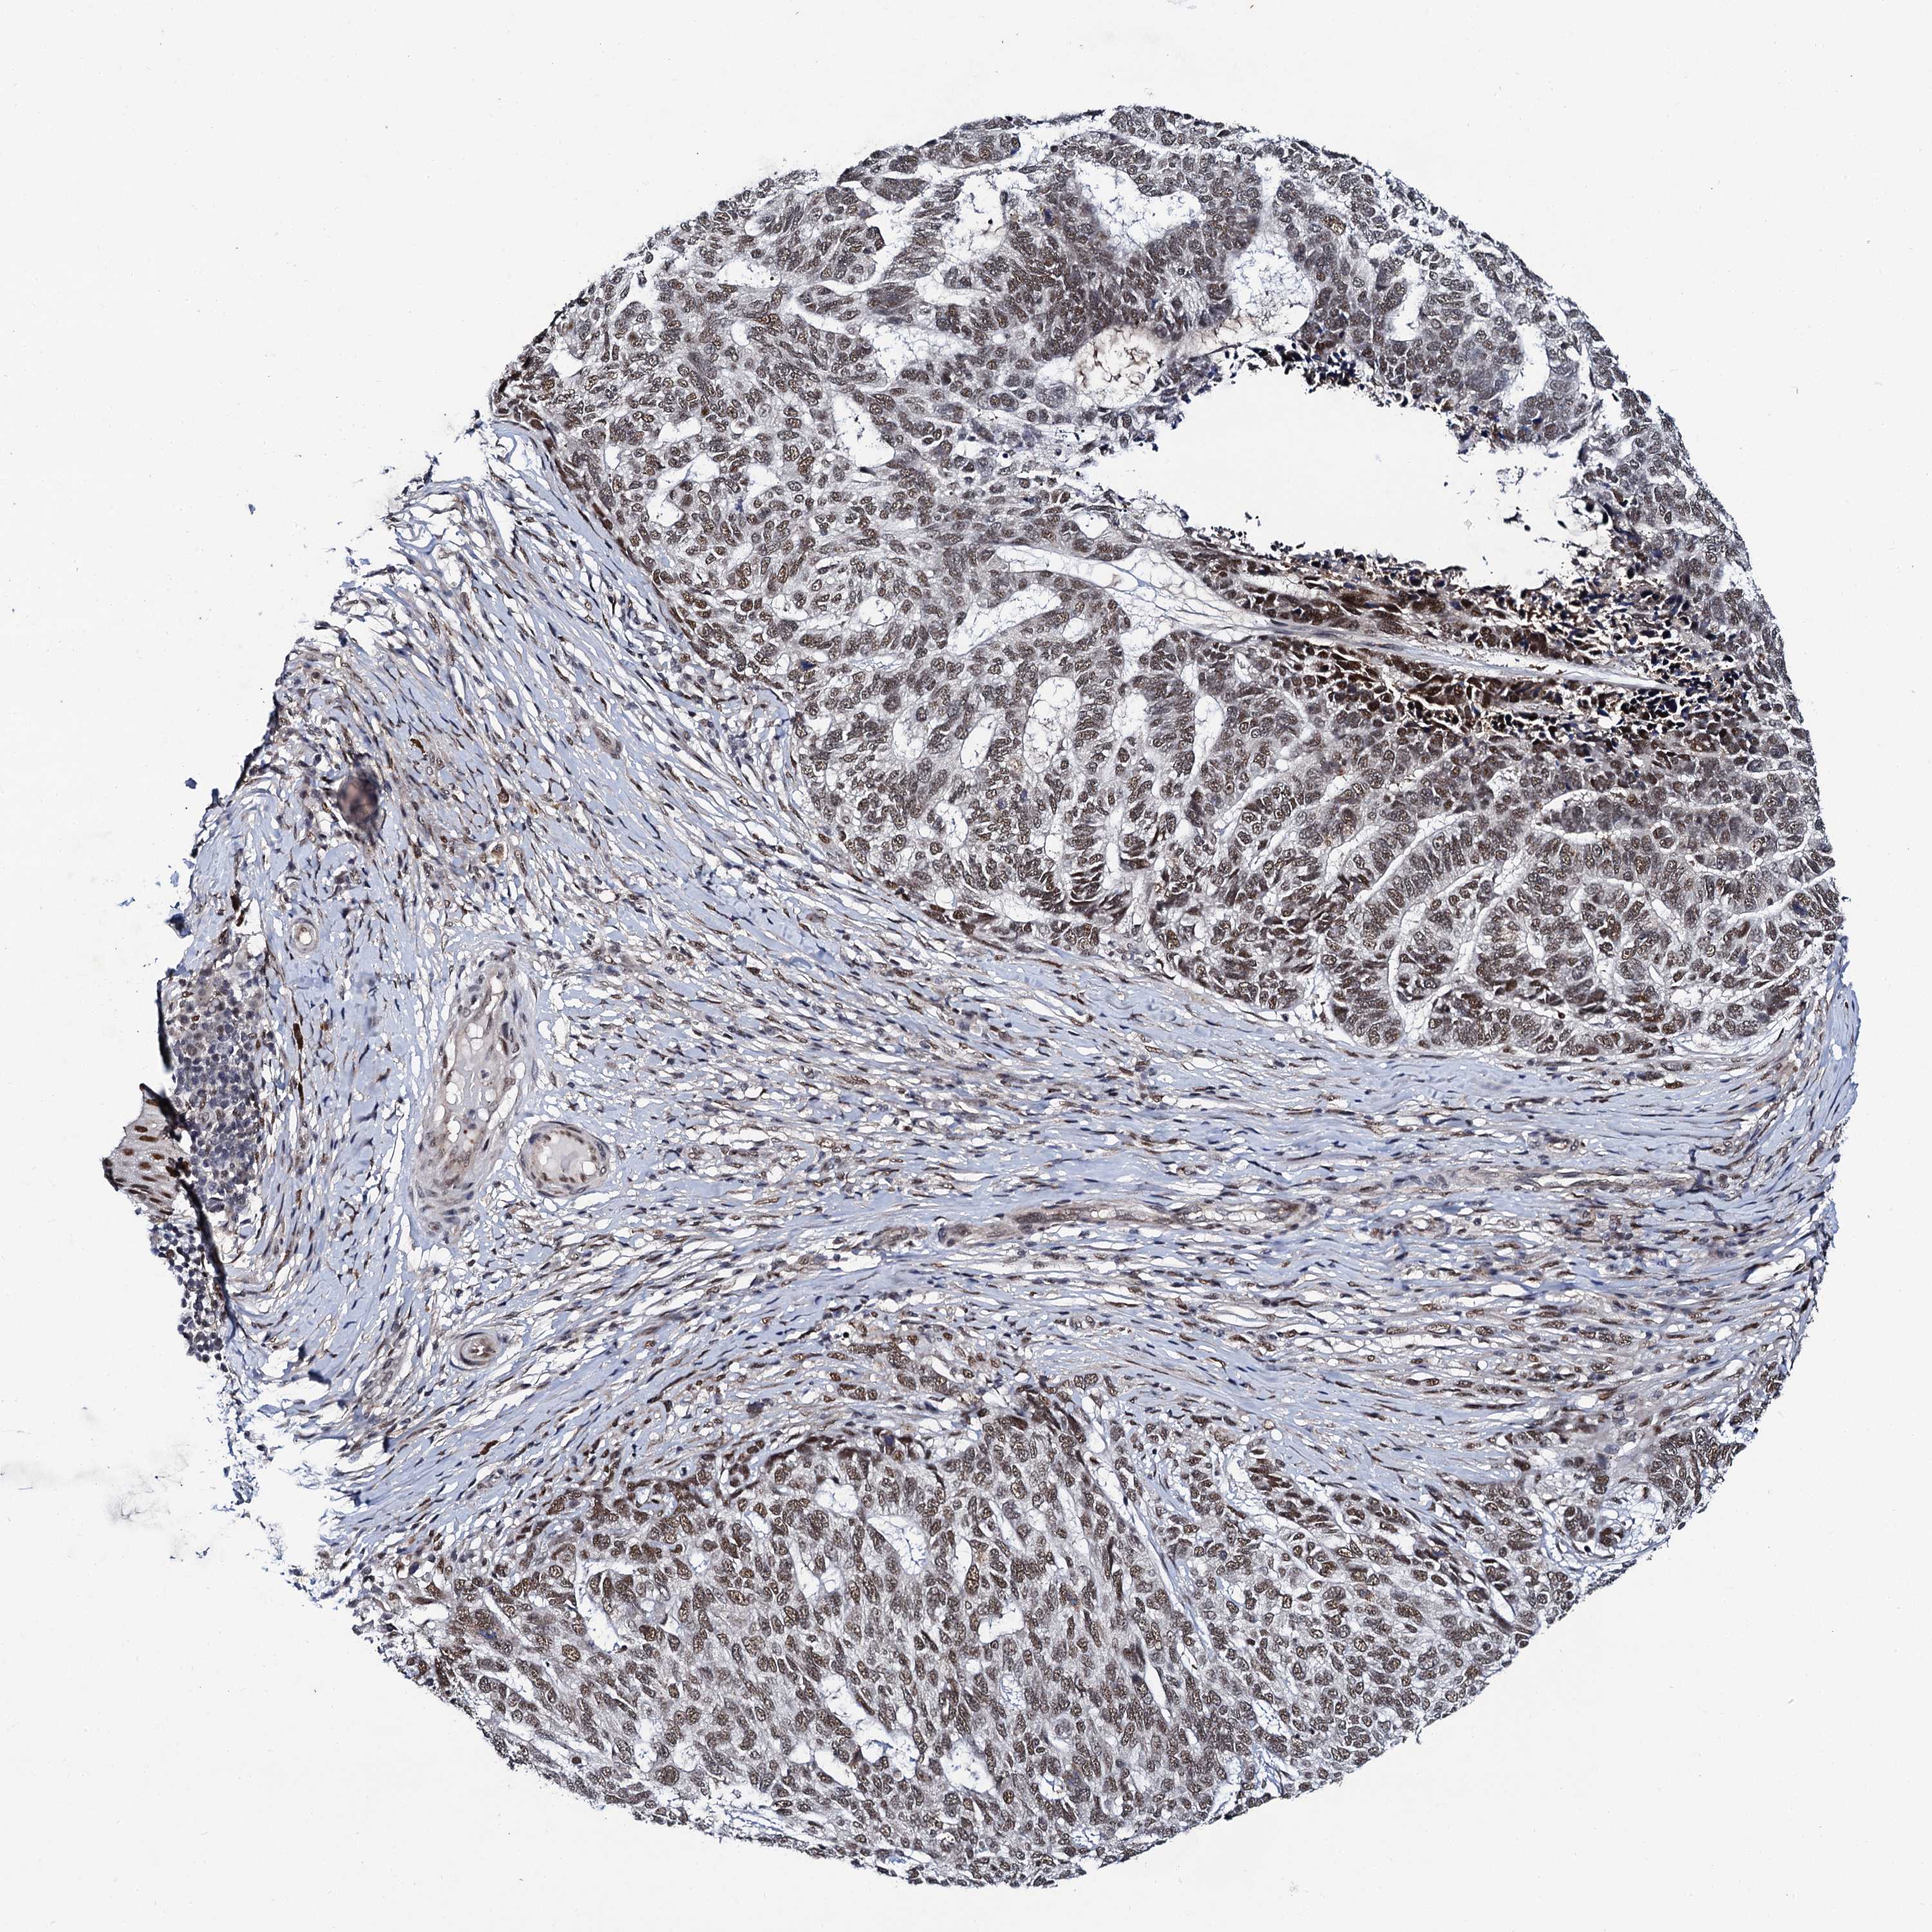

SKIN CANCER - Protein expressioni

A mouse-over function shows sample information and annotation data. Click on an image to view it in a full screen mode. Samples can be filtered based on level of antibody staining by selecting one or several of the following categories: high, medium, low and not detected. The assay and annotation is described here.

Antibody staining in the annotated cell types in the current human tissue is reported as not detected, low, medium, or high, based on conventional immunohistochemistry profiling in selected tissues. This score is based on the combination of the staining intensity and fraction of stained cells.

Each image is clickable and will lead to virtual microscopy that enables deeper exploration of all samples and also displays staining intensity scores, fraction scores and subcellular localization as well as patient and tissue information for each sample.

Antibody HPA040168

Squamous cell carcinoma, NOS